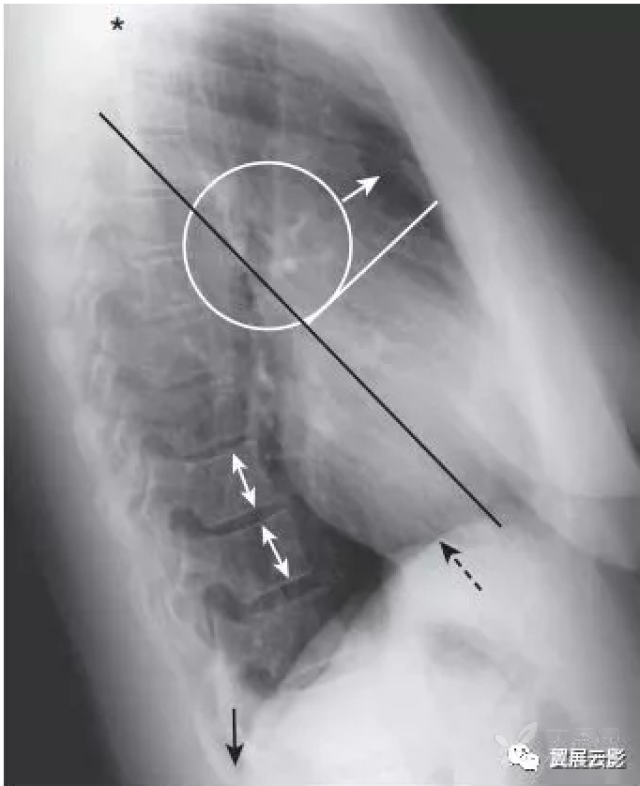

图2-2:正常左侧位x线胸片

侧位胸片,这 5 个关键区域一定要记清

正常心脏后前位及左侧位x线表现